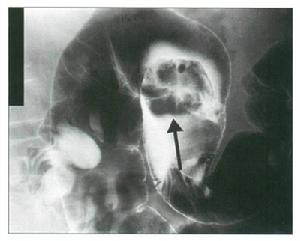

克隆氏病 有重要意義。胃腸道鋇餐造影,能了解克隆病末端迴腸或其他小腸的病變範圍,可見到節段性分布的特徵,病變偏腸系膜緣,小腸黏膜的皺襞增厚、低平或消失和卵石征。X線檢查可與腸結核鑑別,腸結核的刺激征較多見。鋇劑灌腸有助於結腸病變診斷,且常顯示末端迴腸黏膜增粗,結腸管腔狹窄並縮短;潰瘍間有炎性息肉樣充盈缺損,亦有出現瘺管和腸梗阻徵象者。氣鋇雙重造影,可提高小腸或結腸克隆病的診斷率。X線腹部平片,可見腸袢擴張和腸外塊影。

2、X線檢查顯示胃腸道的非特異性炎症,有裂隙狀潰瘍、息肉樣改變、鵝卵石征或多發性狹窄,病變呈節段性分布。